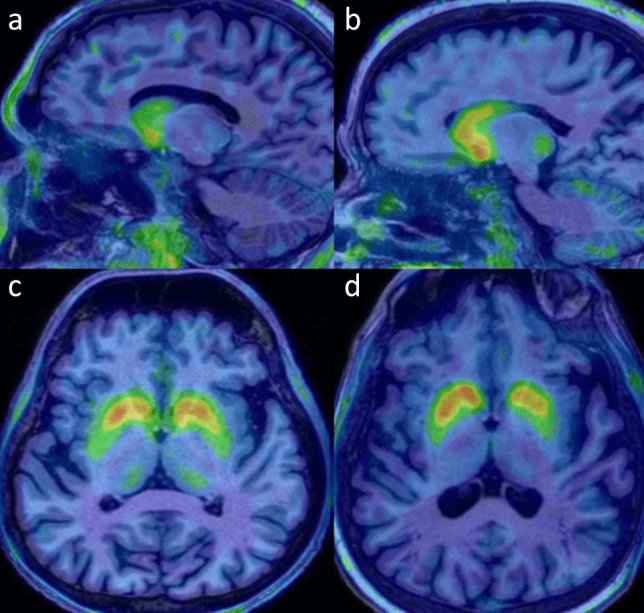

Forty patients (17 with Parkin, 3 with DJ-1 mutations and 20 with IPD) were included. Striatal dopaminergic innervation was assessed semi-quantitatively by 18F-DOPA PET, and cardiac 18F-DOPA uptake was also evaluated. Brain 18F-FDG PET images were evaluated visually. Resting-state functional MRI and diffusion tensor imaging (DTI) were used to assess the BGN activity and WM microstructural alterations.

AR-PD patients showed significantly decreased 18F-DOPA uptake in caudate corpus compared to both IPD and controls, with a more symmetrical striatal dopaminergic denervation. Myocardial 18F-DOPA uptake in AR-PD was similar to controls, while it was significantly reduced in IPD. There was no significant difference in cortical 18F-FDG metabolism and functional activity of BGN between PD groups. The DTI data revealed more extensive WM microstructural damage in AR-PD compared to IPD.

AR-PD group showed additional significant decreased 18F-DOPA uptake in caudate corpus and more symmetrical striatal denervation. Additionally, relatively preserved myocardial innervation, cortical metabolic and WM microstructural changes suggest the possibility of “brain-first” type progression in AR-PD. Also, 18F-DOPA PET/CT may be a practical tool for evaluating dopaminergic innervation of striatum and heart together, but further evaluation is needed in this area.